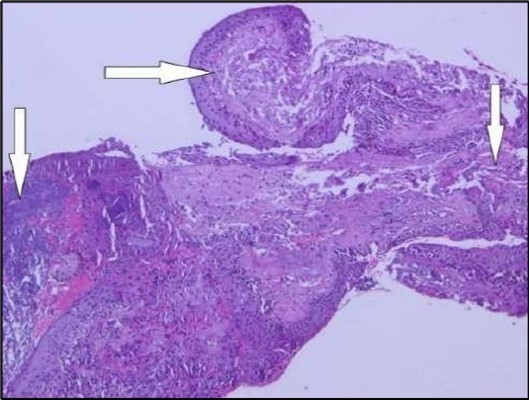

Two weeks post-surgery, the left eye showed significant healing, with a small conjunctival granuloma and vascularization at the ulcer margins. The cornea was clear with a central leading edge nasally, deep and quiet anterior chamber and clear lens. VA 6/6 bilaterally and IOP normal. Histopathology of excised conjunctiva showed non-keratinized squamous epithelium with superficial erosions, stromal elastosis, hemorrhage, and inflammatory infiltration, but no signs of granulomatous disease, malignancy, or viral evidence, findings consistent with idiopathic localized inflammatory process. The patient reported significant relief and satisfaction post-surgery, resuming normal activities. Treatment continued with oral prednisolone 25 milligrams every other day, tobramycin-dexamethasone ointment twice daily, and preservative-free artificial tears four times daily Figure 4, Figure 5a, Figure 5b, Figure 5c, Figure 5d.

Figure 5a.OS, Hematoxylin and eosin (H&E) stained section of the corneal specimen demonstrating full-thickness epithelial loss with underlying stromal necrosis.

OS, Hematoxylin and eosin (H&E) stained section of the corneal specimen demonstrating full-thickness epithelial loss with underlying stromal necrosis.

Histopathological examination revealed a dense infiltration of CD138-positive plasma cells within the excised conjunctival tissue (Figure 5b, Figure 5c, Figure 5d). This finding supports an antibody-mediated immunopathogenesis in Mooren’s ulcer, consistent with Type II and Type III hypersensitivity mechanisms described in the literature 20, 21. The prominent presence of CD138- positive plasma cells provide a clear pathological rationale for conjunctival resection, as excision of the immunologically active perilimbal conjunctiva effectively removes the local 'factory' of autoantibodies that drive corneal stromal destruction, thereby halting ongoing tissue damage 21.